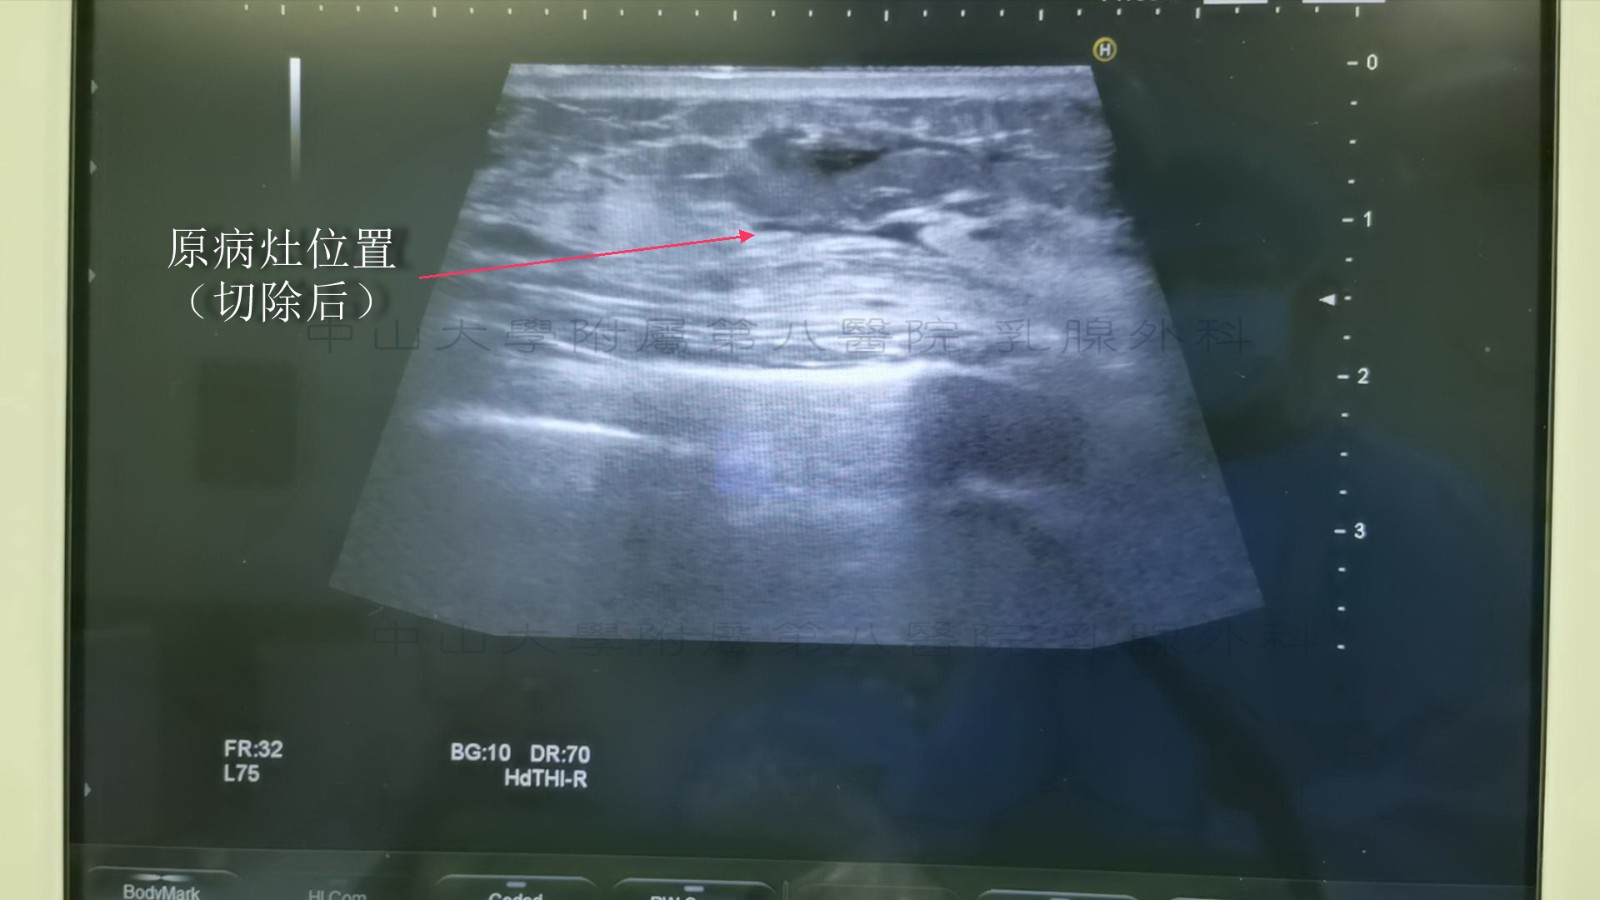

下图示为完成旋切后超声再次检查术区

下图示为肿物切除后的残腔

术后3个月原病灶区域会形成稳定瘢痕,此时复查彩超常会见到原病灶区域异常低回声区。术后6个月瘢痕区域基本完全吸收,此时复查彩超效果较好。